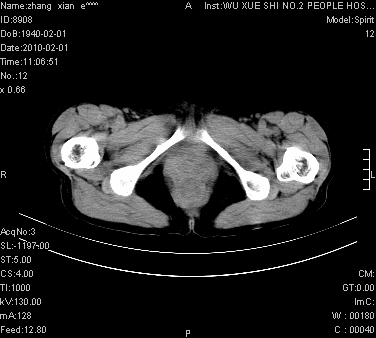

标题: CT24434:70岁 女 腹胀,腹水原因待查 [打印本页]

大量腹水,脾脏囊性占位,子宫颈占位,右侧腹股沟淋巴结肿大,建议+c,先查妇科。

腹盆腔大量积液,子宫增大,子宫颈增大外形不规则,内见低密度影,膀胱后壁显示不清,右腹股沟肿大淋巴结,脾脏囊性占位,子宫颈占位,子宫颈癌?建议增强。